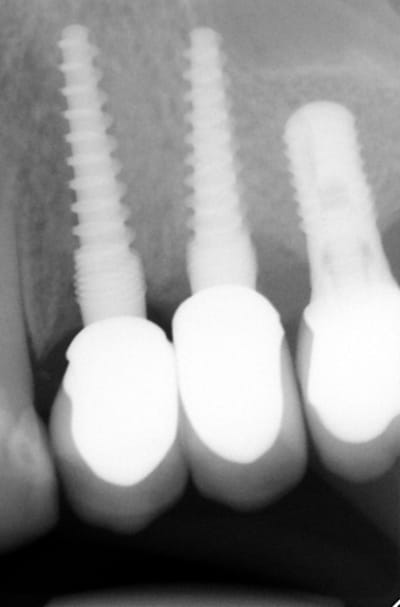

Pour ceux que ca interessent, et parce qu on a m a demandé des cas supplémentaires dans le sujet 23 implants rehabilitation totale, voici un autre cas d implantation immédiate avec la technique minimalement invasive et condensation grace aux forets.

Le patient a reçu un traitement il y a dix ans dans le maxillaire et dans le 4eme quadrant.Comme on peut le voir j´ai du extraire quelques dents au maxillaire: 35 37 et 45.

Le septum de la 37 a été foré avec un foret conique 3 faces.

J ai planté à 60 Ncm sans fracturer le septum.Juste après l opération , les prep caps en zircon ont été cémenté.La restauration définitive 34 jusqu` à 37 été fixé 2 semaines après l implantation avec implantlink (detax). Après un an, le bridge a été retiré facilement pour voir l´état de la gencive et faire une radio de contrôle.On la re ossifiction est satisfaisante et que la gencive "aime" le zircon.

Le bridge a ensuite été recémenté sans correction nécessaire du bridge.